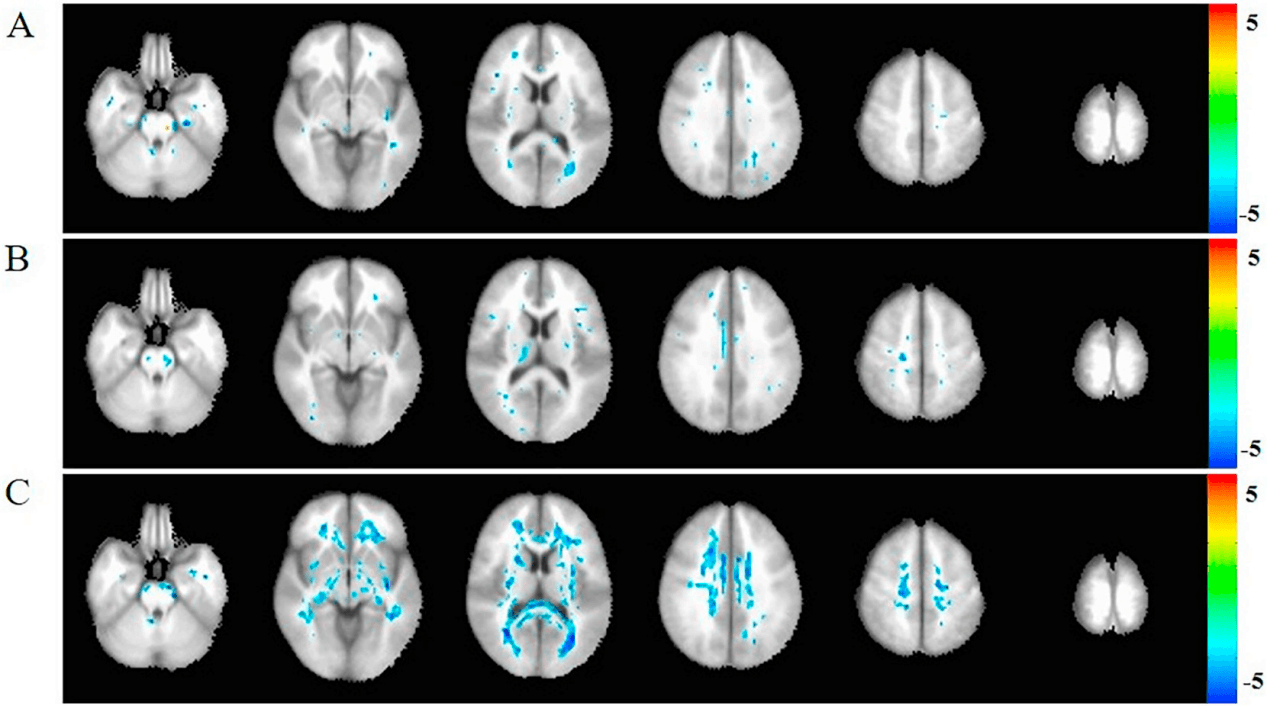

核心算法包括标准化的DTI数据预处理、基于体素的全脑分析(VBA)、基于白质骨架的跨被试统计分析(TBSS),以及确定性与概率性纤维追踪技术,用于构建个体化结构连接网络。

该系统提供完整的DKI数据预处理、基于体素的指标分析,以及基于白质骨架的跨组统计比较(TBSS)。同时,它支持基于DKI模型的确定性纤维追踪与结构网络构建,为研究脑肿瘤、神经退行性疾病等导致的复杂白质微结构变化提供了比传统DTI更具信息量的高级分析手段。